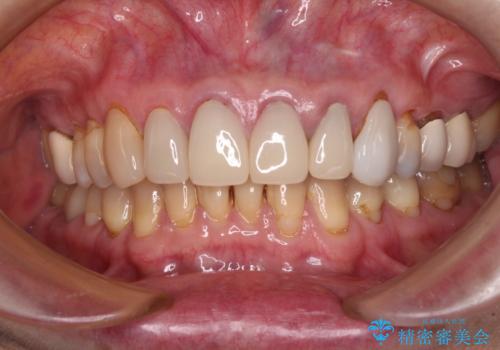

もげてしまった前歯をセラミッククラウンで自然に

- 前歯が土台ごと外れてしまったとのことで来院された患者様です。

土台は外れていましたが破折などの問題はなく、土台からの再治療で対応可能な状態でした。

外れてしまったクラウンを保管しておき、新しいクラウン製作の際に技工所に送ることで、今までと同じような色合いに仕上げることができ、周囲のクラウンとバランスを取ることができます。